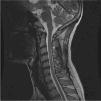

Focalidad neurológica en una paciente con lupus eritematoso sistémico

E. García Melchor, B. Mora Peris, G. Espinosa Garriga

Servicio de Enfermedades Autoinmunes. Hospital Clinic. Barcelona. España